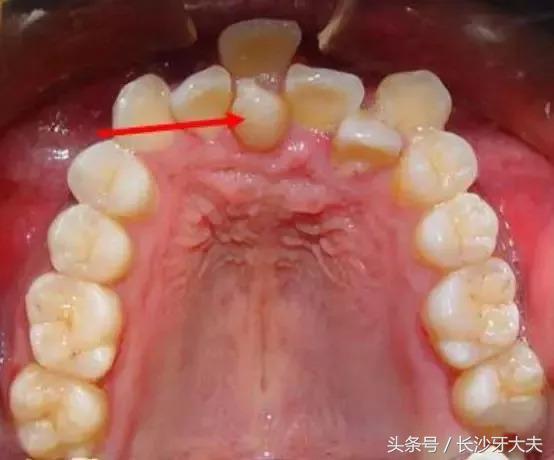

也有些时候,我会复制成普通牙齿的模样混在它们中间,哈哈,分不清哪个是我了吧。

我不喜欢被约束,当普通牙齿都像小士兵一般整齐排队时,我却跑去探索骨内空间了。

偶尔插个小队,挡住去路不让门牙长出来,哈哈,想要从我这过,留下买路钱。